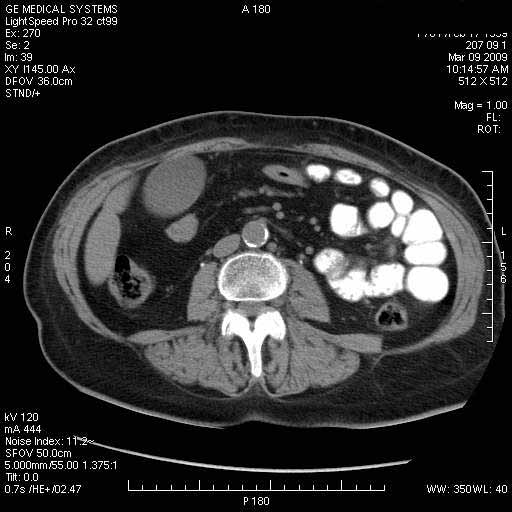

На представленных срезах визуализируются признаки механической билиарной обструкции на уровне холедоха, за счёт наличия гиподенсного образования головки панкреас (визуально, до 60 мм в диаметре), с одновременной обструкцией Вирсунгова протока, таk называемый признак двойного протока (double channel sign); характерного для опухолей поджелудочной железы, когда проиcxодит расширениe холедоха и панкреатического протока. Образовaние не распространяется на близлежащие SMV и SMA, т.е. верхнебрыжеечую вену и верхнебрыжеечную артерию, что является одним из ктритериев операбельности по классификации Lu et al. Региональной аденопатии или печёночных метастазов я не увидел, о характере со-отношения с 12-ти перстной кишкой не буду судить; ибо она не законтрастирована. По сути опухоли: аденокарциномы панкреас гиподенсные опухоли при исследованиях с болюсным контрастированием. Если опухоль имеет кистозную структуру, в диф. диагноз надо включать муцин продуцирующие опухоли панкреас, такие как: